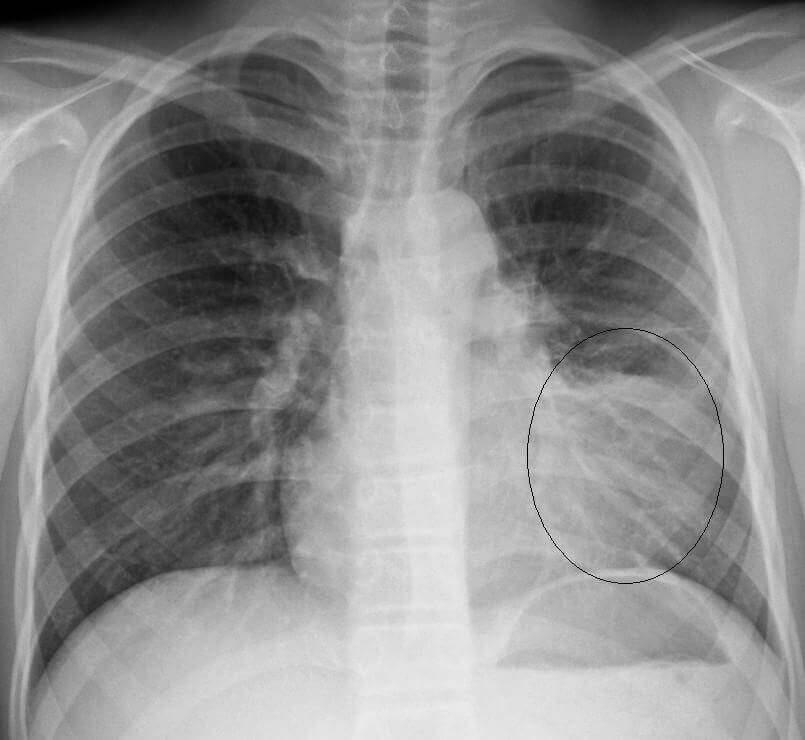

With the help of tests like a chest x-ray and blood tests and physical examination from a doctor can know if an individual is suffering from pneumonia or not.

[lung X beam for pneumonia diagnosis]An X-beam can appear if there is any harm to the lungs.

Chest X-beams can affirm a pneumonia conclusion and show which regions of the lungs are influenced.

A CT sweep of the chest may give progressively point-by-point data.